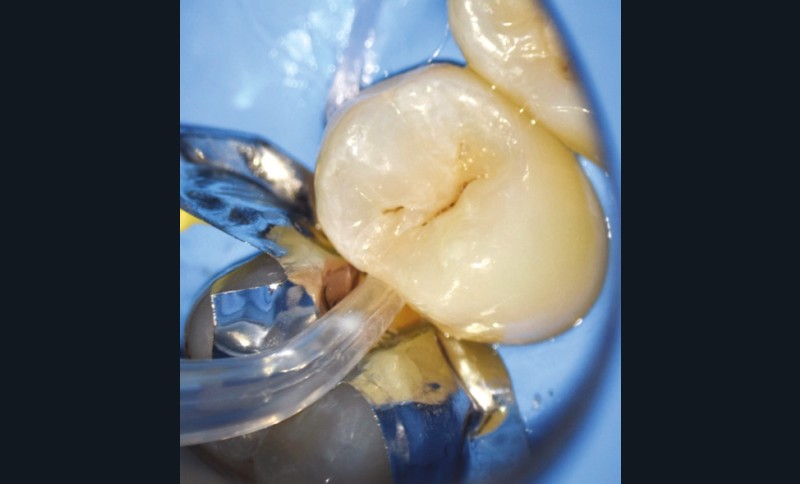

- soit de façon invasive a minima. Cette économie tissulaire peut se faire notamment avec l’utilisation de fraises adaptées et minimalement invasives (fig. 4).

• Traitement invasif a minima : il concerne les lésions carieuses cavitaires ou non avec atteinte dentinaire (à partir du 1/3 moyen dentinaire), soit ICDAS 3 à 6. Dans ce cas, la priorité est de préserver la dent d’une effraction pulpaire éventuelle (recommandations de l’ESE) [4]. C’est pourquoi, lors du traitement de lésions carieuses profondes (ICDAS 4 à 6), il faut dans tous les cas réaliser une éviction sélective, réaliser une préparation a minima (favoriser les préparations de type fente (« slot ») ou tunnel lorsque l’indication se pose) et utiliser un matériau de restauration de choix, soit composite, soit un ciment verre ionomère (CVI), soit des matériaux à base de silicate de calcium ou encore les nouveaux composites enrichis en minéraux (fig. 7 à 9). Ces préparations a minima peuvent être réalisées avec des fraises de petits diamètres (fig. 10 et 11).